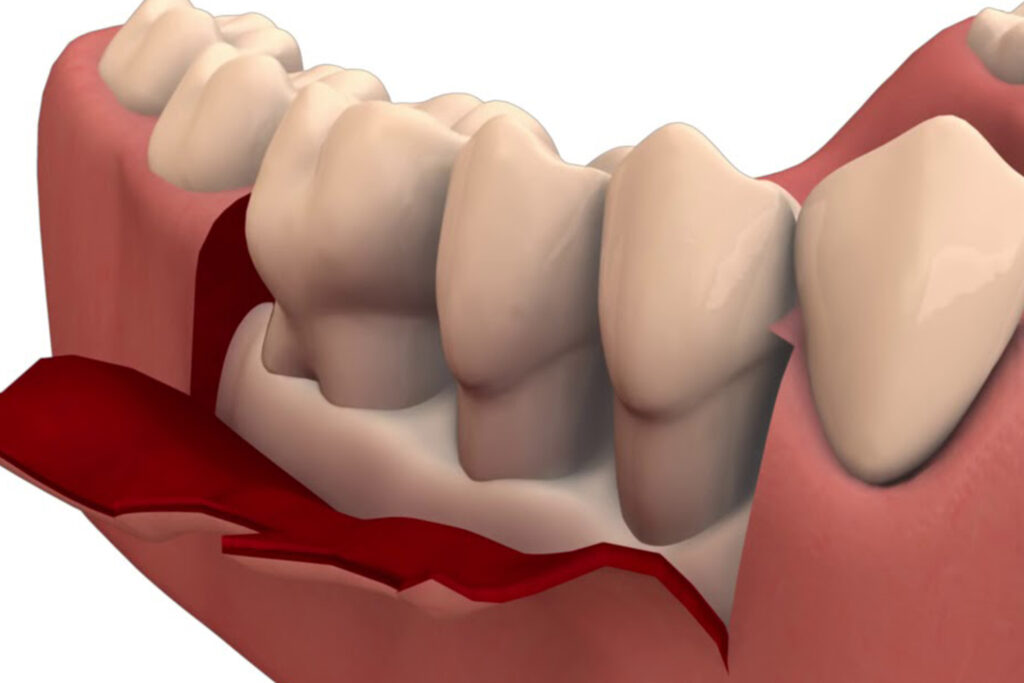

Pocket Reduction

The dentist or periodontist will then use special instruments, such as ultrasonic scalers or hand instruments, to remove the infected tissue and smooth the roots of the teeth. This helps to reduce the depth of the periodontal pockets and encourage healthy tissue growth.